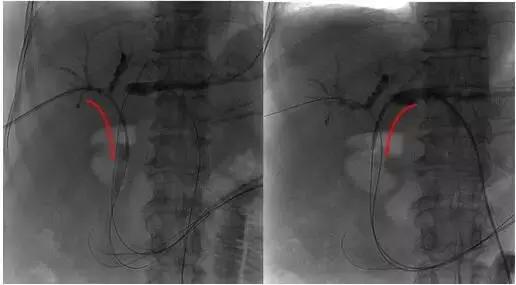

术中DSA下示意图:

2、插入射频消融导管

3、射频消融治疗及支架置入后造影再通